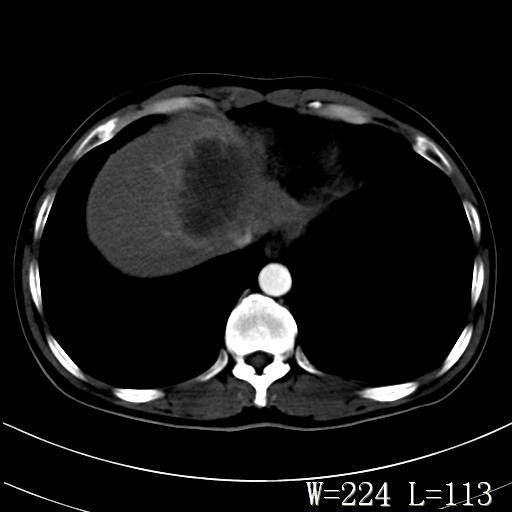

标题: CT27340:肝脏病变? [打印本页]

标题: CT27340:肝脏病变?

男,45岁,发热、乏力半月,午后为主。

对比剂快进快出,首先考虑肝左叶巨块型肝癌。

其次,感染性病变,如肝脓疡不排除。

蜂巢,肝脓肿

蜂巢状,支持!肝脓肿的诊断。